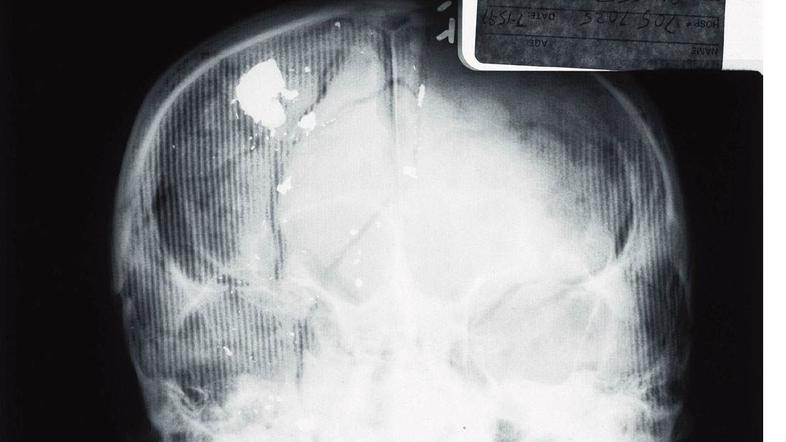

Versaceja je Andrew Cunanan umoril leta 1997 pred njegovo vilo v Miamiju. Modnega guruja je ustrelil v glavo. "O umoru se je veliko pisalo in govorilo. Na tisoče predpostavk, a niti kančka resnice,“ pravi D’Amico, ki je presenečen tudi nad tem, da producenti serije z njim niso navezali stikov.